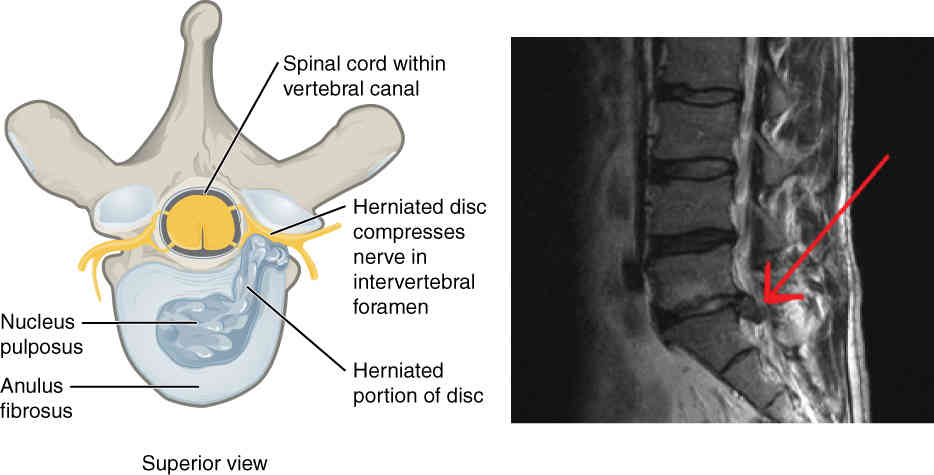

This page is under construction. For now, it is just a resource of the images found in the OpenStax Anatomy and Physiology Handbook. It wil slowly change into a revision tool. Each slide has a number. Use this to refer to the slide. When completed, it will have an unlabelled section, with labelled slides in parallel. On the unlabelled slides, write your answer and use the labelled slide to assess yourself. Keep track by also noting the number on each slide. Improvement at each attempt is important, more so than full marks on a first attempt.